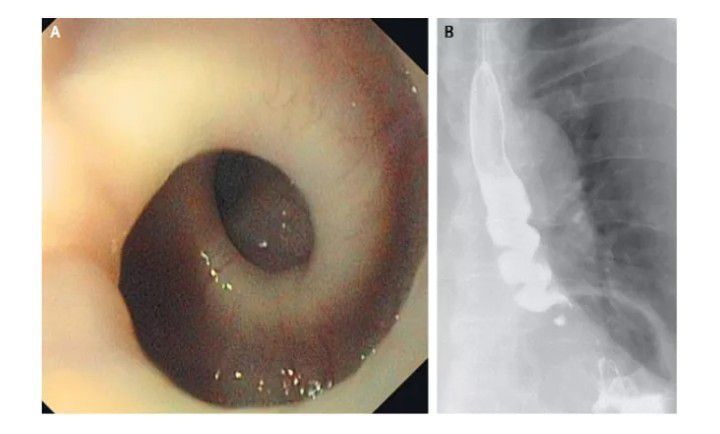

An 87-year-old woman in Switzerland sought medical help when she developed painful spasms every time she swallowed. Imaging and X-rays revealed her esophagus twisted up like a corkscrew whenever she ate. The condition caused her to lose 11 pounds (5 kilograms) over the course of several months. Muscle spasms are to blame for this type of pain. Instead of contracting and relaxing in a series from the mouth to the stomach, the muscles within this woman's esophagus contracted simultaneously, said Dr. John Pandolfino of Northwestern Memorial Hospital in Chicago. There is still no cure for the condition. By: https://www.livescience.com/37919-oddest-medical-case-reports/2.html